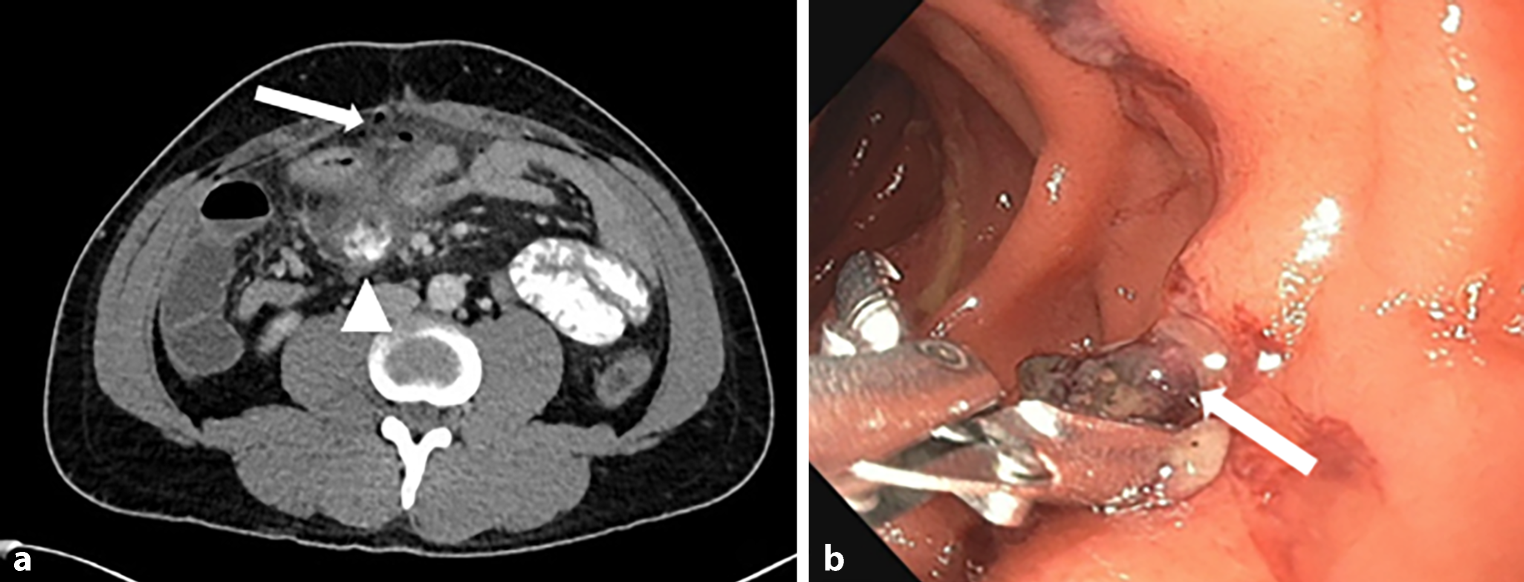

Seven months after the primary operation, the patient again presented to the emergency department with acute and severe abdominal pain. A CT scan (Fig. 1a) now confirmed a free hollow organ perforation with generalized peritonitis. Immediate surgical exploration was indicated. Preoperatively and already under general anesthesia, an esophagogastroduodenoscopy was performed, which revealing a GRENA® clip that had partially migrated into the duodenal lumen (Fig. 1b), causing an intraabdominal fistula from an abscess cavity to the duodenum.

Fig. 1

a Axial CT scan of the abdomen. Arrow showing free air in the abdominal cavity and signs of acute peritonitis. Arrowhead showing inflammatory process suggestive of abscess formation at the duodenum. b Gastroscopic view. Arrow showing the polymer clip protruding into the duodenum at the tip of endoscopic grasper